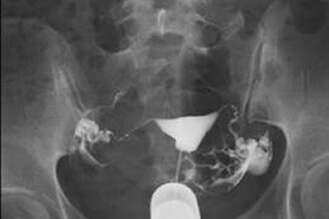

雙側輸卵管水腫不通